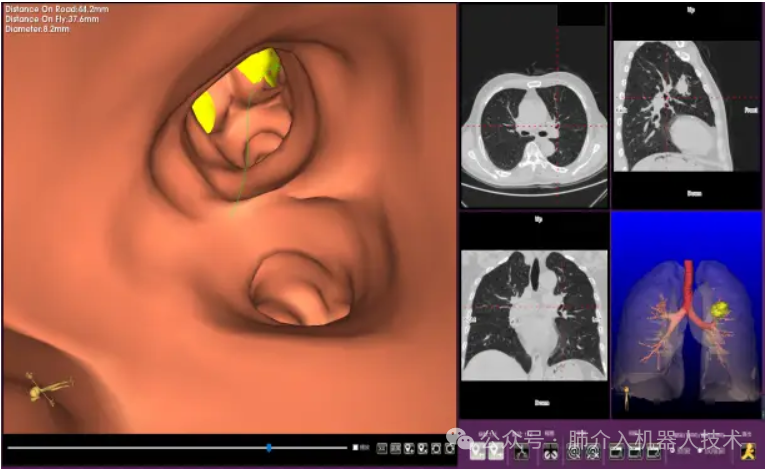

03、奧泰康助力肺部穿刺手術(shù)導(dǎo)航系統(tǒng)獲證

2024年1月31日,經(jīng)國(guó)家藥品監(jiān)督管理局公示,蘇州朗開(kāi)醫(yī)療技術(shù)有限公司自主研發(fā)的肺部穿刺手術(shù)導(dǎo)航系統(tǒng)(國(guó)械注準(zhǔn)20243010222)獲得NMPA批準(zhǔn)上市,奧泰康助力本項(xiàng)目注冊(cè)申報(bào)服務(wù),系2024年奧泰康助力獲得的首張三類醫(yī)療器械注冊(cè)證。

25、醫(yī)達(dá)健康IQQA®極星干將™2號(hào)Robot智能穿刺導(dǎo)航定位機(jī)器人獲批上市

2024年8月,由醫(yī)達(dá)健康自主創(chuàng)新研發(fā)的IQQA®極星干將™2號(hào)Robot智能穿刺導(dǎo)航定位機(jī)器人通過(guò)國(guó)家藥品監(jiān)督管理局(NMPA)注冊(cè)審核,并獲得第三類醫(yī)療器械注冊(cè)證,奧泰康負(fù)責(zé)臨床試驗(yàn)服務(wù)。